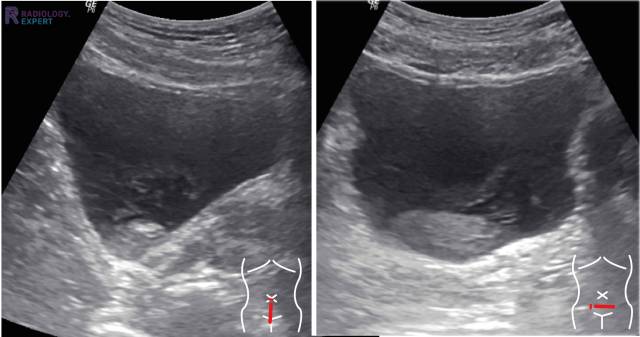

De echografist gebruikt een apparaat dat geluidsgolven uitzendt. Deze golven botsen tegen de organen en weefsels in je lichaam. De echo's die terugkomen, worden opgevangen en omgezet in een beeld op een scherm. Zo kun je zien hoe je blaas en nieren eruitzien, of er geen gekke dingen zitten en of alles goed functioneert.

Je kunt vaak direct meekijken op het scherm. Dan zie je allemaal vage grijstinten. Misschien snap je er niks van, maar de dokter weet precies wat hij ziet.